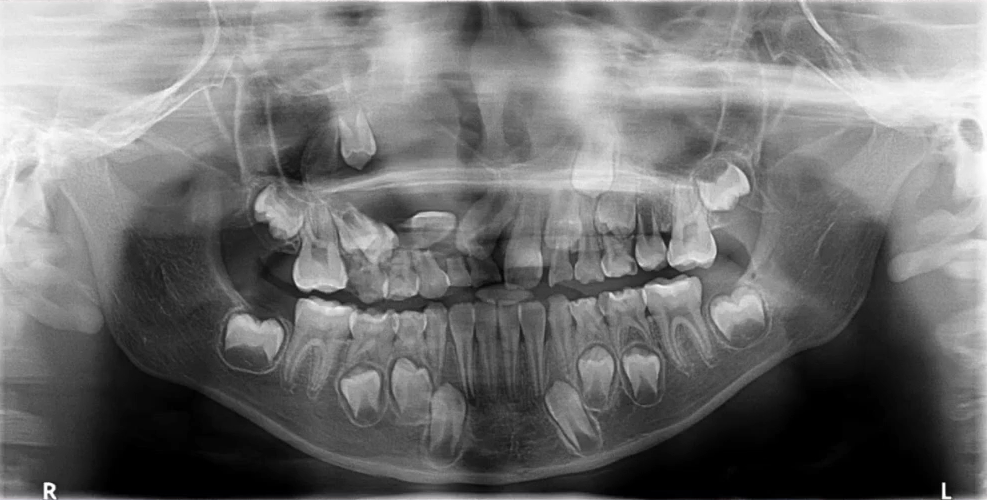

2. 混合牙列期:乳牙情况、恒牙胚观察

曲面断层片拍摄时体位相对比较简单,小患者的配合程度相对高一些。

上颌前牙区、下颌前牙区牙位辨认

患者处于混合牙列期,可以看到右侧前牙区有多生牙,下颌有融合牙的存在。